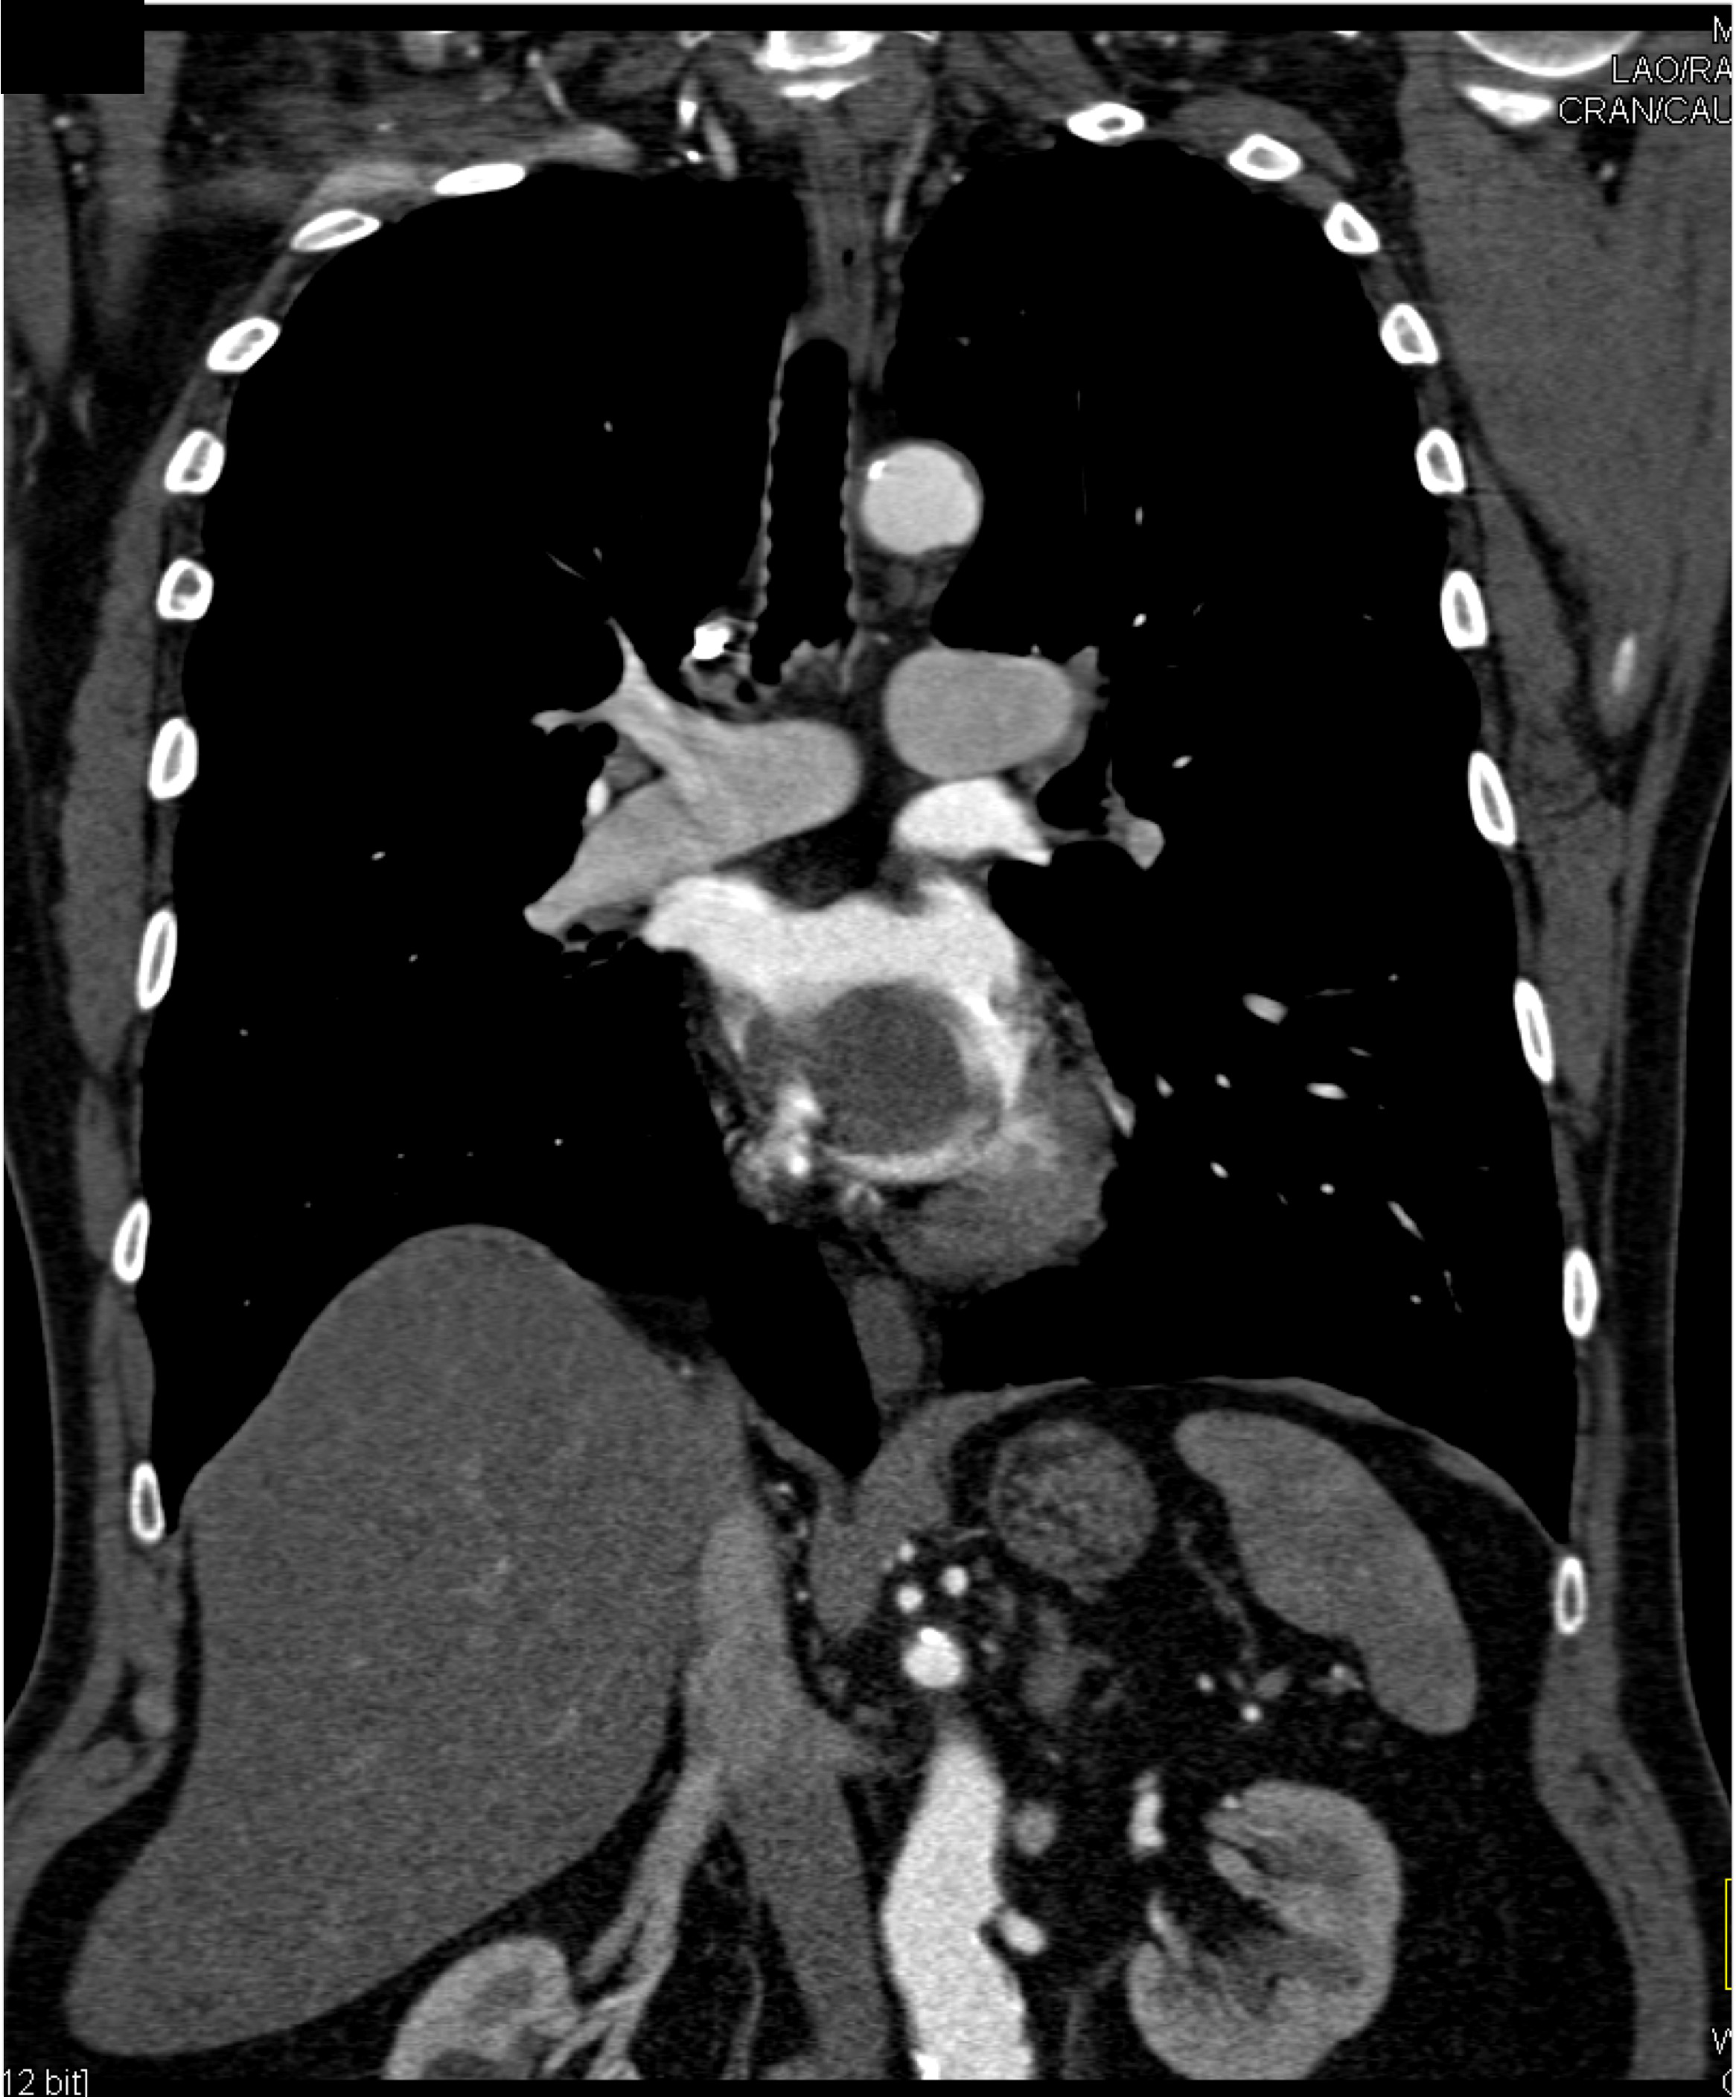

2) The differential diagnosis in this case includes?

FMD (fibromuscular dysplasia)

SAM (systemic arterial mediolysis)

Takayasu’s aortitis

all of the above